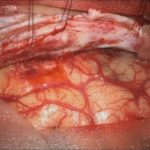

術中写真